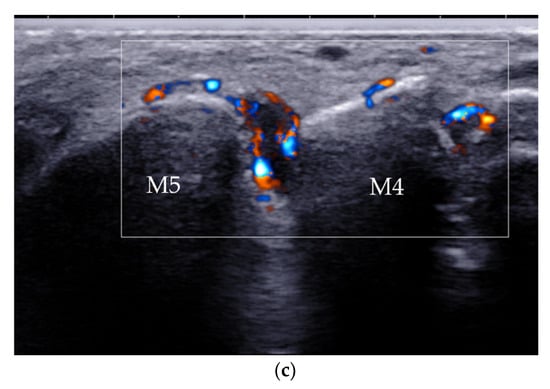

4.2.3. Intermetatarsal Bursitis

| Intermetatarsal bursitis | intermetatarsal spaces between 2nd and 3rd toes | hypoechoic mass with increased vascularity, compressible |